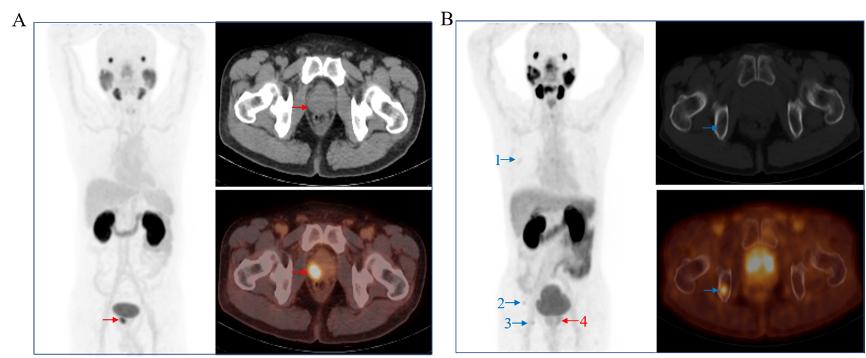

杨志及其团队合影杨志的主要研究领域是生物医药中的放射性药物领域,他“立足临床,服务临床”,进行新型放射性药物的研发及临床转化,在药物研发过程中充分考虑药物的成药性和可商业化,为新型探针的成果转化奠定基础,有效推动核医学逐渐从肿瘤治疗的“幕后”步入“台前”。目前他已开发肿瘤诊疗药物二十余种,实现成果转化4项,合同转让金额近6300万元。将CD20抗体(美罗华)进行99mTc标记,已成功应用于寻找乳腺癌、黑色素瘤、骨与软组织肿瘤等的前哨淋巴结。创新性地开发了集传统18F和68Ga标记探针优势为一体的Al18F-PSMA-BCH,临床试验有效证实了该类探针的稳定性和有效性,该探针已进行临床试验4500余例,已获得国家药品监督管理局核准签发的《药物临床试验批准通知书》,并成功豁免Ⅱ期临床试验,目前正在开展Ⅲ期临床试验。针对该靶点,和北京大学第一医院杨兴教授团队合作,通过改变探针的结合核心基团,获得了PSMA-P137系列探针,可降低膀胱的放射性摄取,有望用于前列腺癌的精准诊疗。过氧化氢酶标记上β治疗核素177Lu并与海藻酸钠混合得到177Lu-Cat(ALG),可用于实体肿瘤的局部放射性内照射治疗。

Al18F-PSMA-BCH PET/CT 为前列腺癌的精准诊断提供基础

177Lu-Cat(ALG) 用于骨与软组织肿瘤的内照射治疗